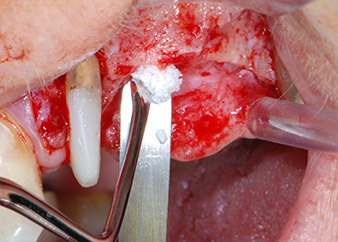

Avant la pose de l'implant, les tissus infectés ont été retirés de l'os alvéolaire sur le site de l'implant et autour des dents piliers à l'aide d'un insert initialement conçu pour le façonnage de l'os et la récupération des copeaux d'os (Piezomed, insert B5) (Figures 6 et 7).

Les défauts osseux autour des implants, sur la face mésiale de la dent 27 et autour de la racine de la dent 24, ont été reconstruits par des particules de substitut osseux xénogénique et recouverts d'une membrane collagène résorbable (Bio-Gide, Geistlich Biomaterials) pour une augmentation par GBR (Fig. 13 et 14).